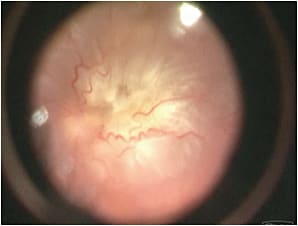

The study was further categorized with regard to PVR stage. Grade A PVR was defined as vitreous haze or vitreous pigment clumping, while Grade B PVR included wrinkling of the inner retinal surface, a rolled edge of a retinal break, or retinal stiffness (Figure 1, page 32). A full-thickness retinal fold, or a star fold in one area, was considered to be Grade C-1 PVR (Figure 2, page 32). PVR ranged from Grade 0 (no PVR) to Grade C-1, and all of the patients had at least three months of follow-up. To our knowledge, this was the largest study of patients with RRD: 181 surgeons from 48 countries provided information on 7,678 RRDs. Most of the results from this study group have already been published.1-4

Figure 2. Intraoperative view with a BIOM shows PVR C retinal detachment. Full-thickness retinal fold is being removed with a forceps.